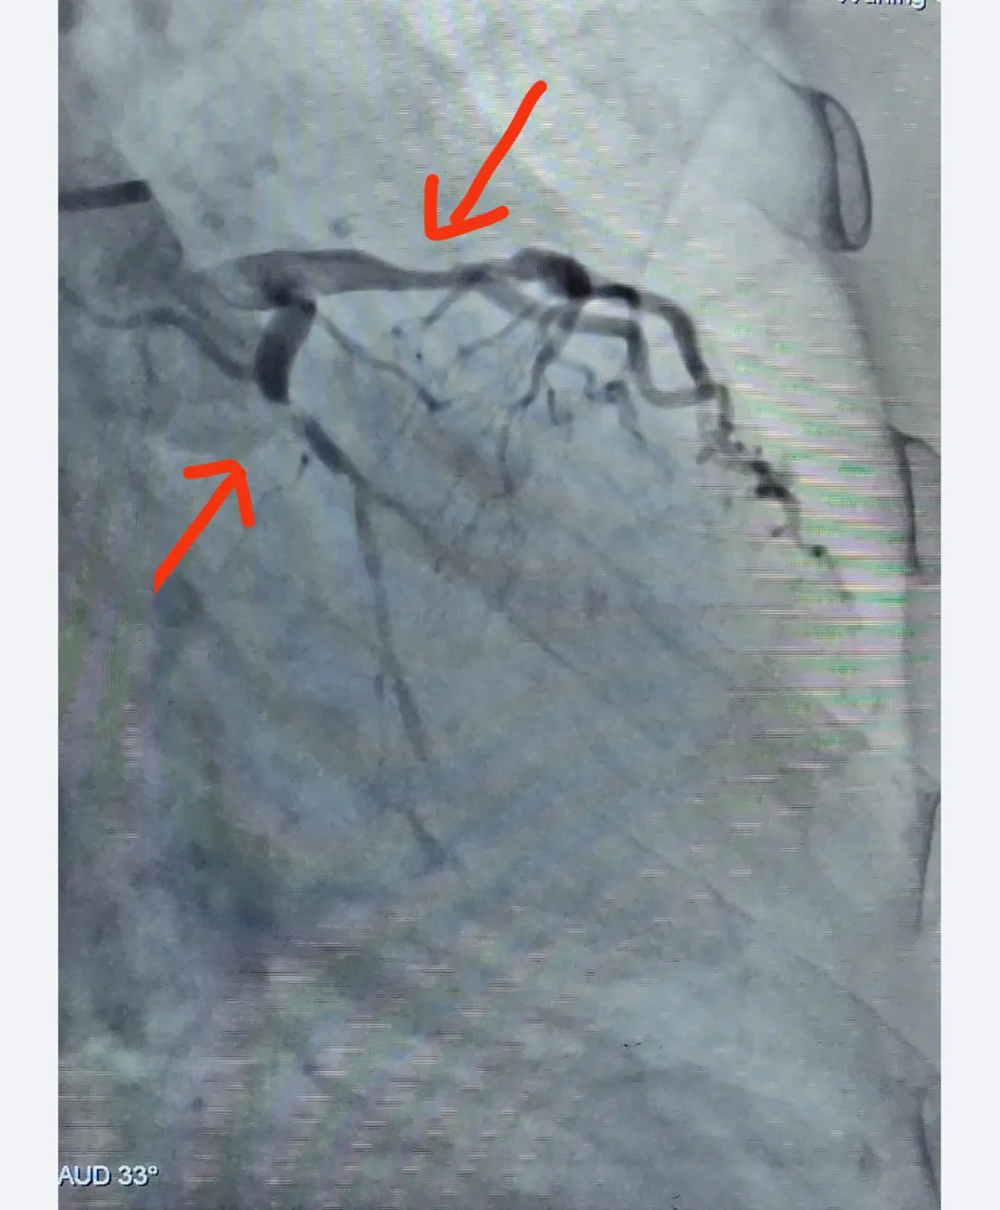

手术前

支架植入后